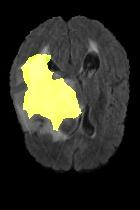

Current unsupervised anomaly localization approaches rely on generative models to learn the distribution of normal images, which is later used to identify potential anomalous regions derived from errors on the reconstructed images. However, a main limitation of nearly all prior literature is the need of employing anomalous images to set a class-specific threshold to locate the anomalies. This limits their usability in realistic scenarios, where only normal data is typically accessible. Despite this major drawback, only a handful of works have addressed this limitation, by integrating supervision on attention maps during training. In this work, we propose a novel formulation that does not require accessing images with abnormalities to define the threshold. Furthermore, and in contrast to very recent work, the proposed constraint is formulated in a more principled manner, leveraging well-known knowledge in constrained optimization. In particular, the equality constraint on the attention maps in prior work is replaced by an inequality constraint, which allows more flexibility. In addition, to address the limitations of penalty-based functions we employ an extension of the popular log-barrier methods to handle the constraint. Comprehensive experiments on the popular BRATS'19 dataset demonstrate that the proposed approach substantially outperforms relevant literature, establishing new state-of-the-art results for unsupervised lesion segmentation.